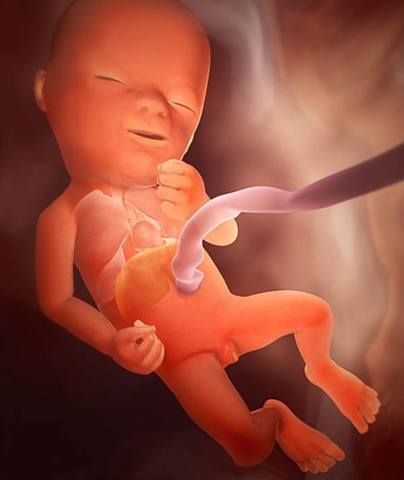

El cigoto se convierte en embrión. desarrolla el sistema circulatorio, el corazón y brotes de lo que posteriormente serán los brazos y piernas. presenta una cola que es el inicio del cordón umbilical. Se forman los dedos de las manos y pies, los labios, el hígado, orejas y ojos.

Las uñas empiezan a crecer y los huesos a endurecer, los riñones producen orina y los órganos sexuales empiezan a desarrollarse.

Comienza a crecer el cabello y los órganos sexuales interno se ubican en la posición de la cadera

Crece un bello fino en el cuerpo y una capa de grasa que ayudará a proteger la piel del bebé cuando nazca.

Aparecen pestañas y cejas.

Inicia cambios físicos, regula actividades y momentos de sueño, los parpados se abren y se forma la retina.

El vello o lanugo se cae, y en el sexo masculino los testículos inician el descenso al escroto.

El feto tiene mas grasa corporal, las pupilas se contraen al exponerse a la luz.